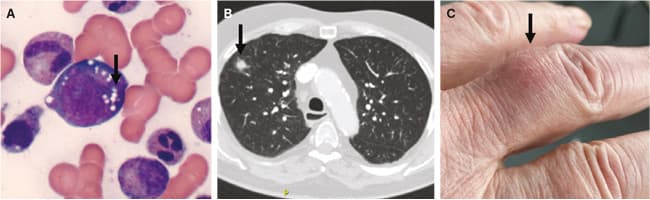

A. Udstrygningspræparat af knoglemarv fra patient med VEXAS, hvor de klassiske cyto­plasmatiske vakuoler i en myeloid progenitorcelle kan ses (pil). Præparatet er farvet med May-Grünwalds eosinmetylenblå farvning. B. CT af lungerne hos en patient med VEXAS med uspecifik infiltrativ forandring i højre lunge (pil). C. Kutan nodulær forandring typisk for patienter med VEXAS (her lokaliseret på tredje venstre finger) (pil).